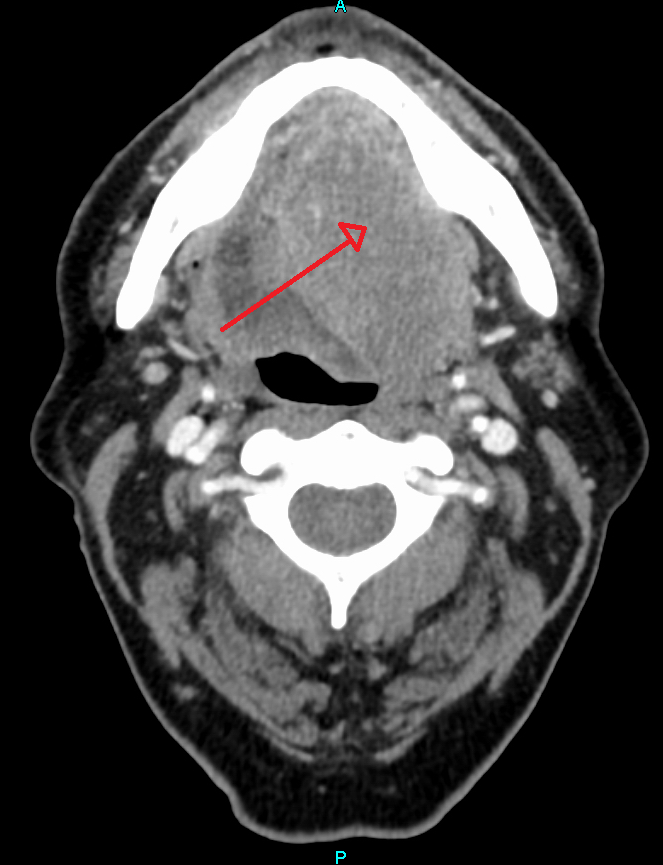

2. 1. 두경부

두경부암(구강, 비강, 비인두, 인두 및 관련 구조의 암) 사례의 약 90%[4]가 편평상피세포암(SCC)으로 인해 발생한다.